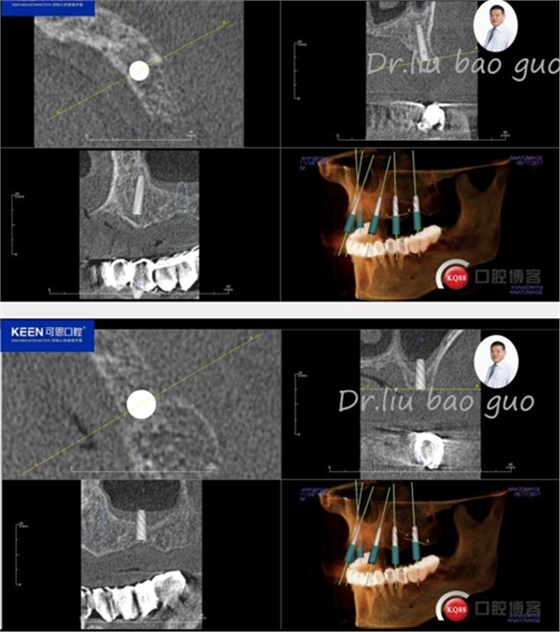

手術(shù)前種植軟件設(shè)計(jì)方案

數(shù)字化種植導(dǎo)板設(shè)計(jì)及制作